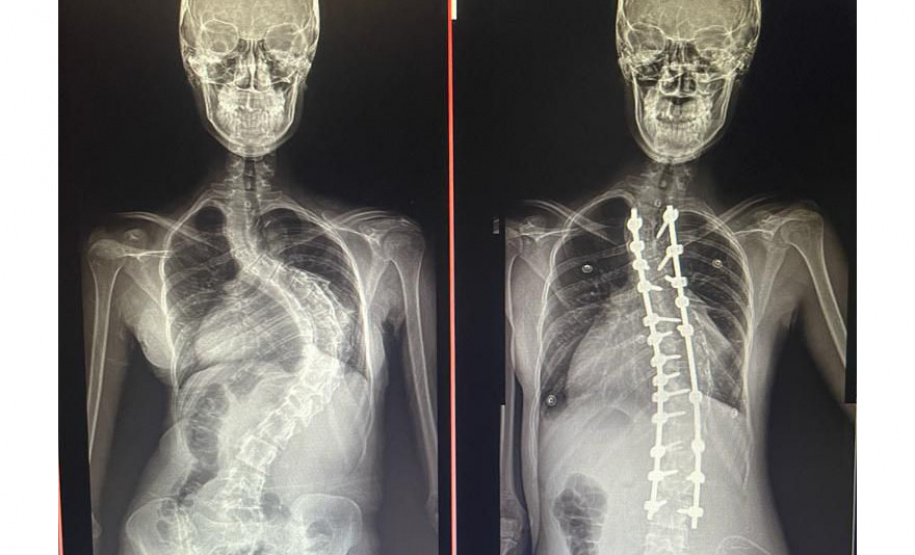

Aos 14 anos, a adolescente Milena de Andrade Carvalho, moradora de Guaratuba, no Litoral do Estado, foi diagnosticada com escoliose idiopática. Sem causa definida, esse tipo de escoliose pode surgir a partir dos quatro anos até a adolescência e ocorre durante o estirão de crescimento. Quando a condição da curvatura ultrapassa os 40 graus, a escoliose se torna progressiva e o paciente continua entortando. Essa condição ocorre com maior frequência em meninas e é muito importante que os pais estejam atentos a qualquer sinal do problema.

“Descobrimos a escoliose por acaso, nunca tínhamos percebido a deformidade, até que um dia ao amarrar meu biquíni, minha mãe observou que eu estava com a coluna torta e ao passar a mão percebeu a curvatura. Decidimos então procurar atendimento médico e tive o diagnóstico da doença já com 50 graus de curvatura e indicação imediata de cirurgia”, contou a adolescente.

Outro tipo de escoliose é a causada por doenças neuromusculares, como paralisia cerebral, mielomeningocele, distrofia muscular, atrofia muscular espinhal, entre outras. No caso do Lucas Batista da Paixão, de 18 anos, a paralisia cerebral que teve ao nascer foi o que desencadeou a condição. Com curvatura acima dos 100 graus, desconfortos respiratórios como falta de ar e asma, a posição do adolescente na cadeira de rodas estava bem limitada.